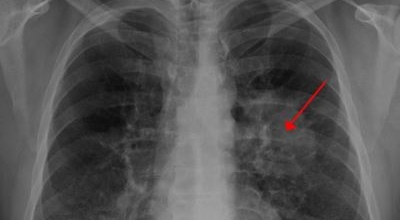

폐암 초기증상

2. 폐암 초기증상 - 기침

기침은 폐암 초기 증상 중 가장 일반적으로 나타나게됩니다. 폐암 환자의 75% 정도가 잦은 기침을 호소하는데 감기로 인한 것과 비교가 어려워 그냥 넘기는 경우가 풍부하므로 조심하는 것이 좋습니다. 그러니 기침이 긴 시간 계속되는 경우 반드시 진찰을 받아보시기 바랄게요.